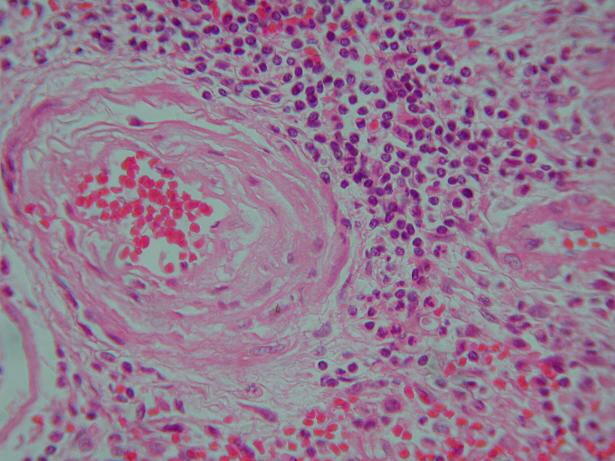

6.血管腔内の赤血球 HE染色